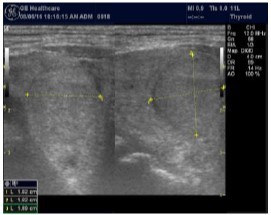

In our study many patients were found to have nodules look very much like PT adenoma, Figure 7 below. At least, 4 patients were subsequently confirmed to have parathyroid adenomas, Figure 8 and 2 patients underwent surgery

Despite the fact that nodular pathology was found to be very prevalent among our study population, it has been found difficult to differentiate between thyroid and parathyroid pathology using ultrasound alone. However, some characteristics of the parathyroid glands might suggest parathyroid pathology in the context of the clinical picture of secondary or tertiary hyperparathyroidism which is very prevalent in ESKD patients’ populations.

Figure 7.Thyroid nodule suspicious for Parathyroid adenoma due to its location

Figure 8.Nodule that proven to be a parathyroid adenoma, volume =5265 mm3

There are 4 parathyroid glands (2 superior, 2 inferior) imbedded within the thyroid gland. The parathyroid glands are bean-like shape and small (20-40 mg) 25. Sonographically, the parathyroid glands have the following features 25:

Hyperplastic glands: hypoechoic, volume <500 mm3.

Nodular glands: hypoechoic. Volume >500 mm3

Histologically, if the excised gland has volume <500 mm3 it is said to be hyperplastic and if the volume is more than 500 mm3 it is nodular hyperplasia in 80% of cases26. In secondary HPT, the increase in the volume of parathyroid glands is associated with increase in vascularity, as evident in Color Doppler imaging 27.